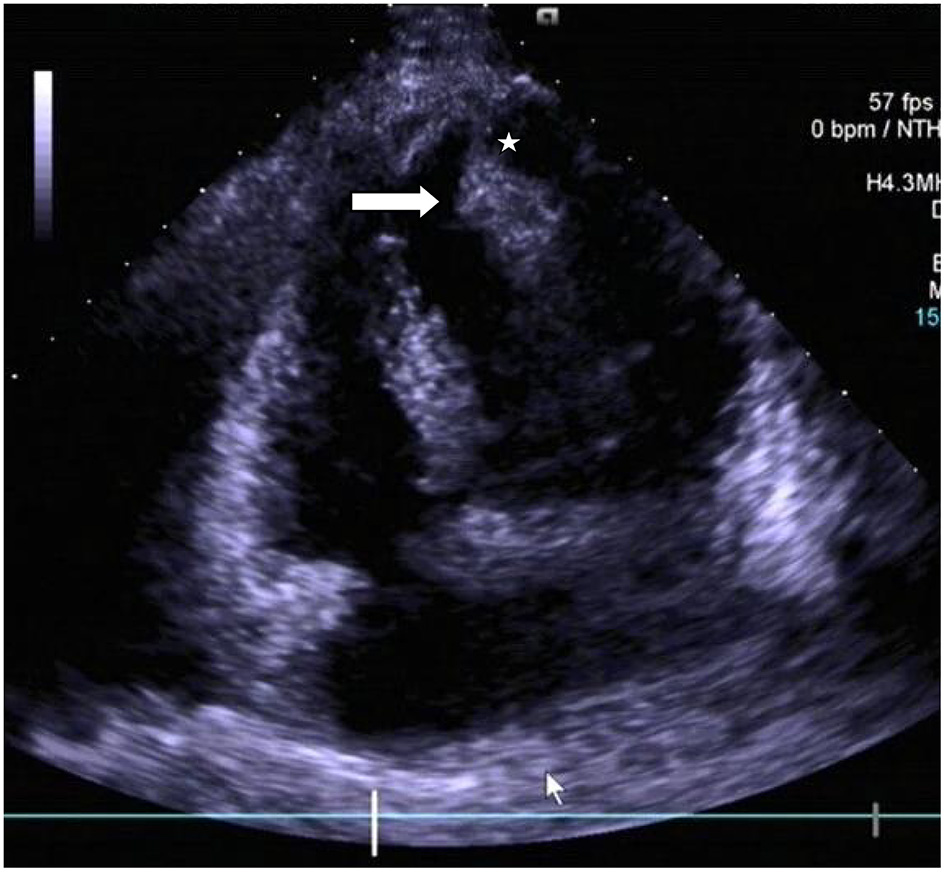

Chest radiograph showed a moderately enlarged cardiac silhouette with increased cardiothoracic ratio and no signs of pulmonary congestion. Transthoracic echocardiogram (TTE) examination showed the following characteristics: aorta 34 mm, left atrium 35 mm, LV cavity 51 mm (end-diastolic diameter), and a hyperechoic mass 30 × 27 mm located on the left side of the heart (middle-apical region), occupying almost 2/3 of the LV with blood supply from the left anterior descending (LAD) coronary artery (Figure 1). The vast mass caused a marked dilatation of the LV with mild to moderate LV outflow tract (LVOT) obstruction and decreased ventricular ejection. In addition, the apical and diaphragmatic part of the tumor was mildly calcified. CT scan of the chest confirmed a mass measuring 28 × 32 mm (Figure 2). The hyperechoic mass was highly mobile, with a peduncle measuring ~4 cm in diameter, adhering to the apical diaphragmatic surface of the LV free wall and papillary muscle.

Figure 1

Transthoracic echocardiogram revealing the presence of a pedunculated lobular mass [peduncle (asterisk); mass (arrow head)] within the left ventricle.